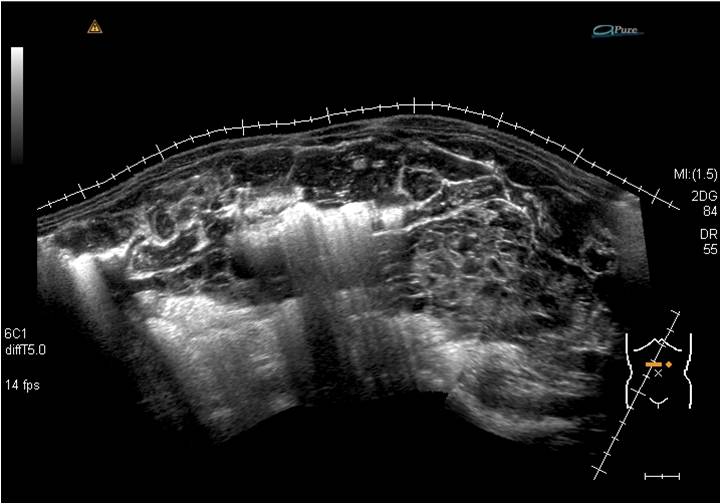

インパクトイメージング賞

氏 名 : 丸山 憲一

所 属 : 東邦大学医療センター大森病院

診断名: 『腹膜偽粘液腫』

装 置 : 東芝AplioXG 3.5MHzコンベックスプローブ

対 象 : 30歳代男性

コメント:腹腔内に貯留する粘液の分布状態をイメージできるよう、横断面での連続像を

パノラミックビューにて表現。消化管は腹腔内に充満した粘液により圧排をうけており、

食思不振の原因と考えられた。 |